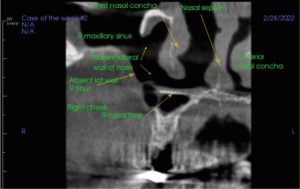

Initial examination of the scan volume with a coronal slice through the R cheek, maxillary sinus and nasal septum revealed 1) Absent R lateral wall of nose, 2) Absent R lateral wall of maxillary sinus.

Figure 1. Coronal section Right cheek and maxillary sinus